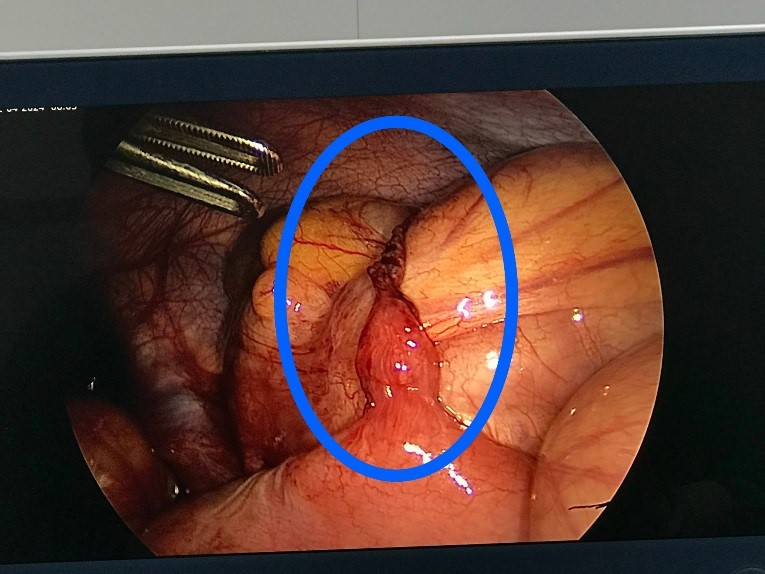

Hình 3 (

hình ảnh trong mổ Nội soi): dây

chằng vắt qua gây nghẹt ruột

Cả 2 trường hợp trên đều được các Bác sỹ khoa

Ngoại tổng hợp – Bệnh viện Trẻ em Hải Phòng tiến hành phẫu thuật nội soi. Trong

quá trình phẫu thuật, các Bác sỹ phát hiện có 1 dây chằng vắt qua 1 quai ruột

gây nghẹt ruột, các quai ruột phía trước giãn to, phù nề, xung huyết nhiều –

đây là nguyên nhân chính gây tắc ruột. Ca phẫu thuật diễn ra nhanh chóng, chỉ

sau 30ph đã giải quyết được tình trạng tắc nghẽn, lập lại được lưu thông đường